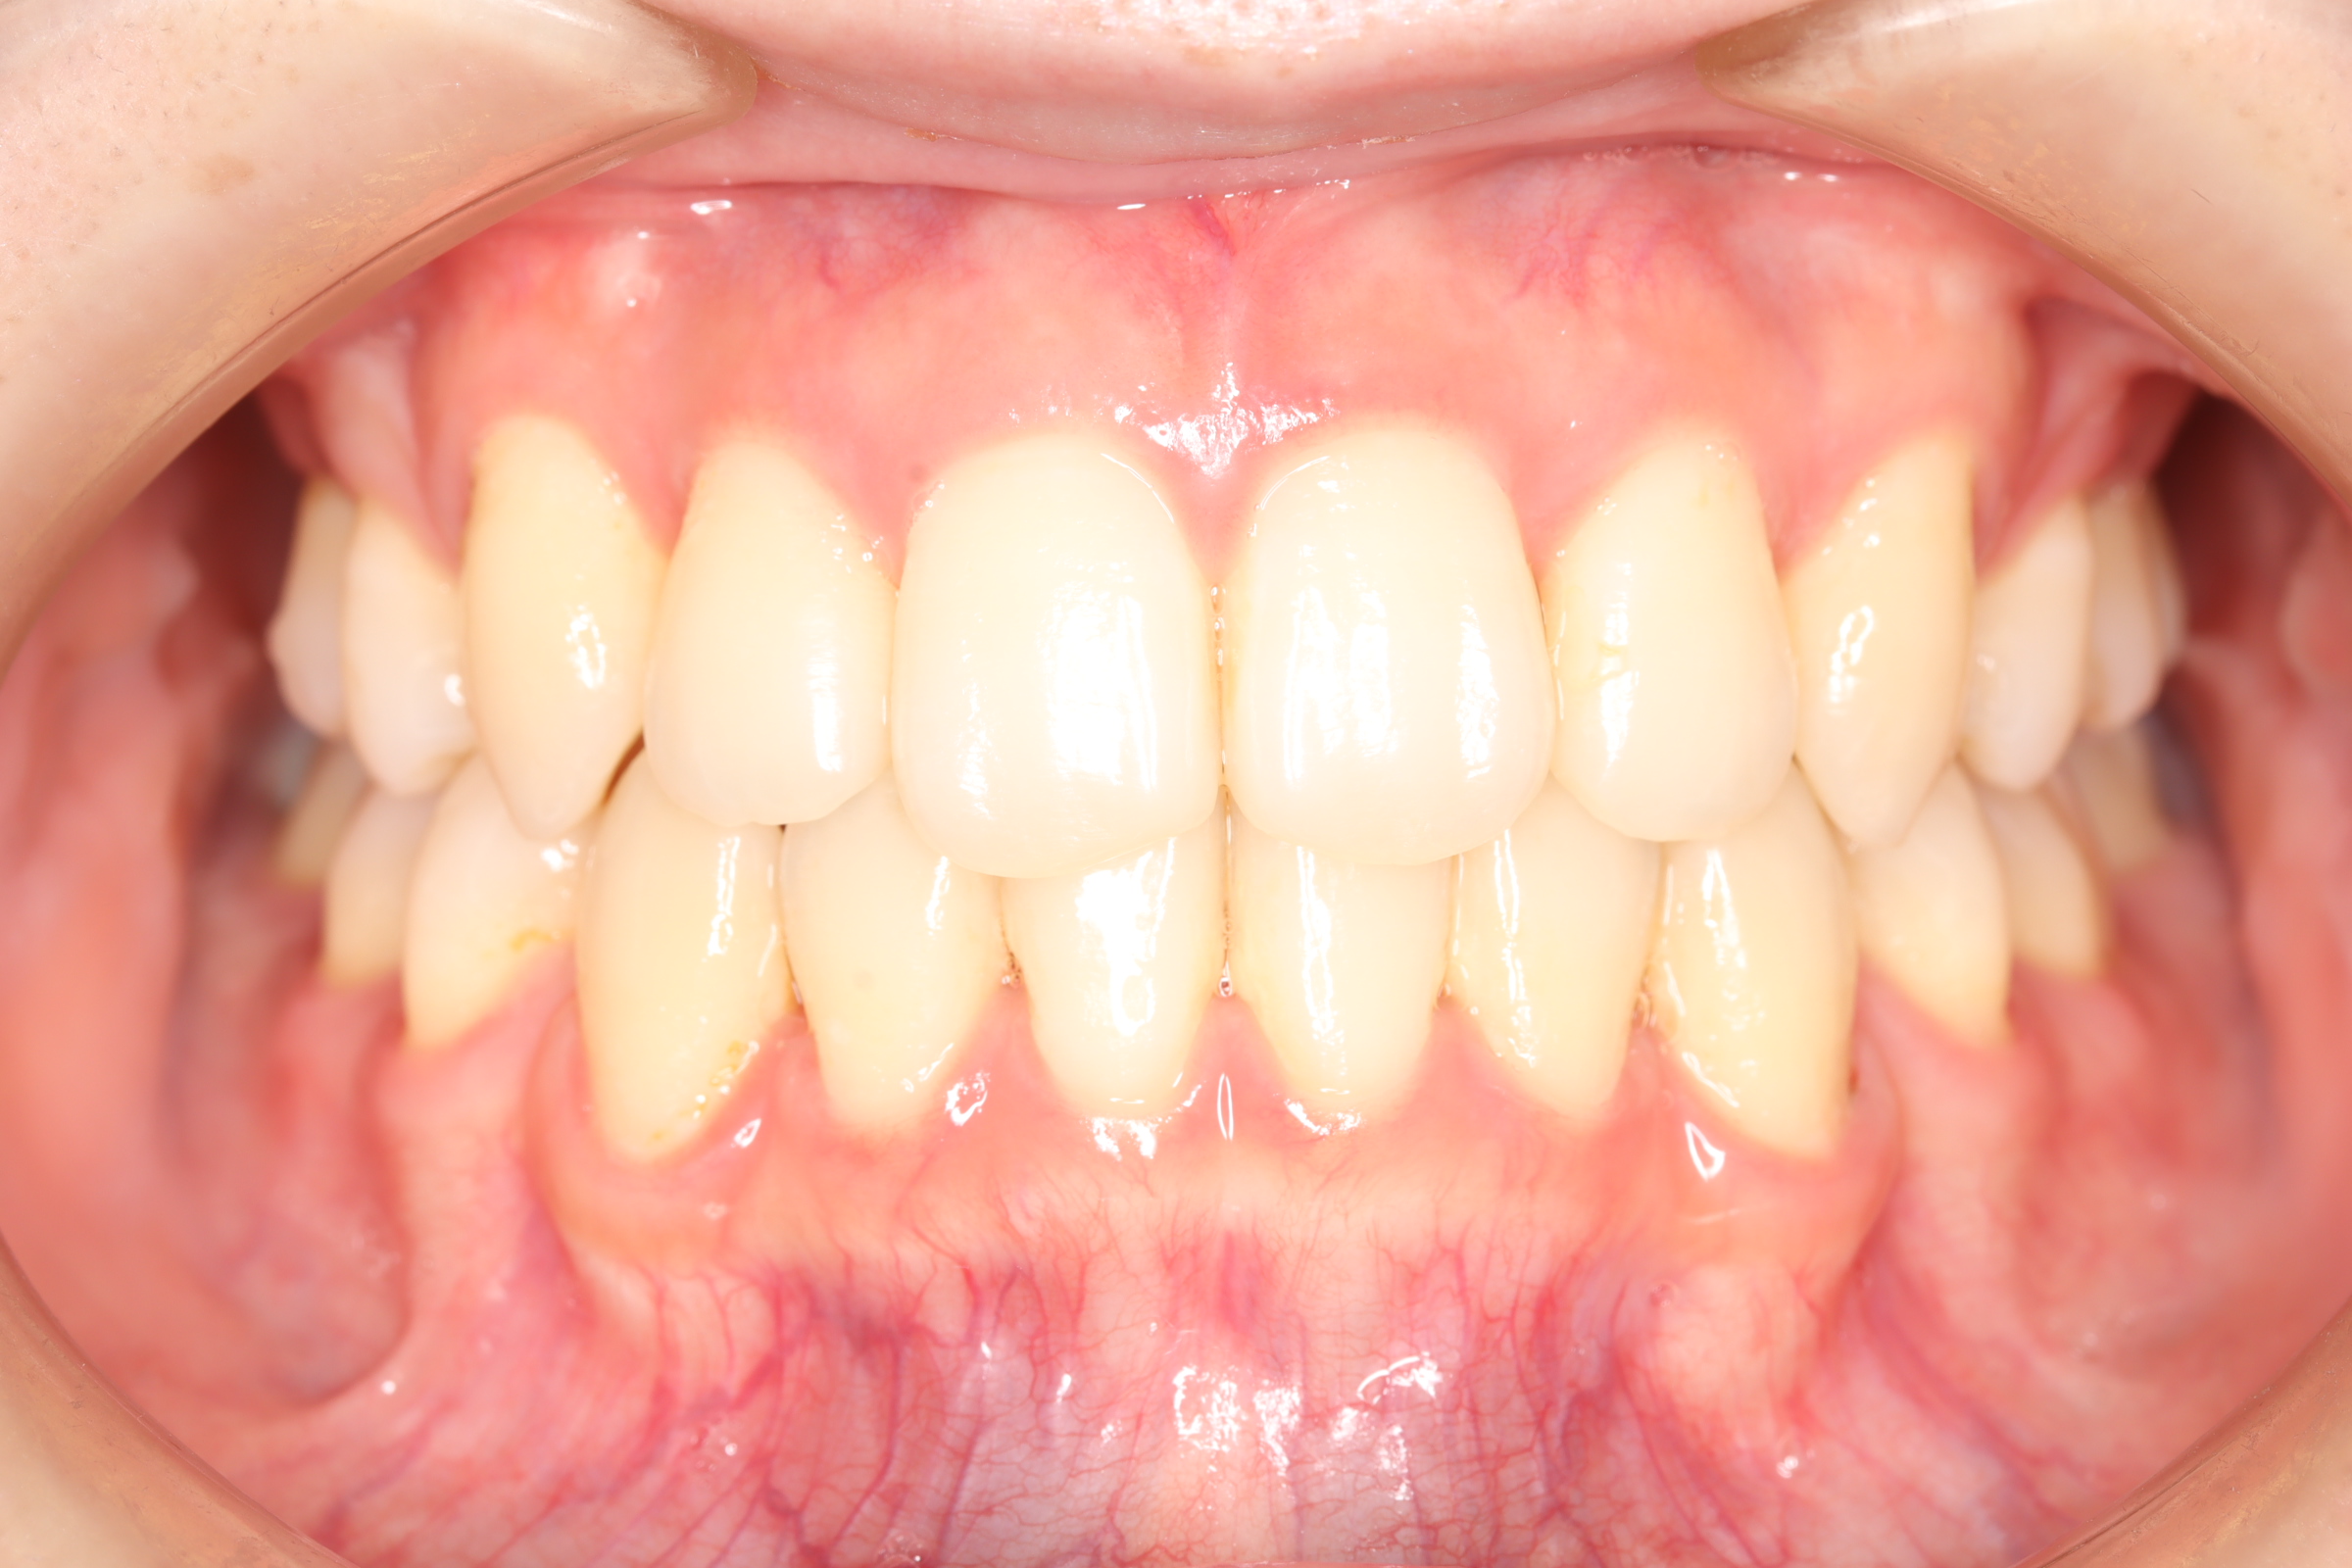

舌側(リンガル)矯正での叢生(ガチャ歯)の治療

口腔内の変化

| 治療前 | SNSなどで「ガチャ歯」と呼ばれている、見た目のがたつきを治したかった患者さんです。 骨格的な問題はありませんでしたが、上下の前歯が唇側傾斜しており、上下顎前突症で口元の突出感がありました。 |

| 治療後 | 前歯から奥歯まで全体的に緊密な咬み合わせになっています。 歯のガタつきが無くなることにより、綺麗な見た目と歯磨きのしやすい口腔内環境になりました。 また突出感のあった口元もすっきりして綺麗なEラインとなり横顔も変化しました。 しっかりとしたかみ合わせを作ることにより、綺麗な歯並びになります。 |